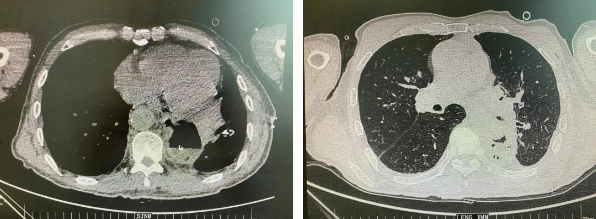

近日,胸科醫(yī)院執(zhí)行院長(zhǎng)李小飛教授帶領(lǐng)胸外科一病區(qū)團(tuán)隊(duì)完成一臺(tái)復(fù)雜胸外科手術(shù):食管癌與肺癌同期手術(shù)。

患者王某不幸同時(shí)患食管癌與左肺癌,病理類型系雙源發(fā)腫瘤,食管為鱗癌、肺為腺癌。食管癌和肺癌為胸外科最常見(jiàn)的疾病,但同時(shí)患兩種疾病,十分罕見(jiàn)。家屬輾轉(zhuǎn)多個(gè)醫(yī)院,得知李小飛院長(zhǎng)擅長(zhǎng)胸外科復(fù)雜手術(shù),慕名來(lái)西安國(guó)際醫(yī)學(xué)中心醫(yī)院。

經(jīng)過(guò)李小飛教授、李文海副教授、穆強(qiáng)副主任醫(yī)師團(tuán)隊(duì)積極準(zhǔn)備,排除手術(shù)禁忌;經(jīng)過(guò)全科術(shù)前充分討論,大家認(rèn)為:如果分兩次進(jìn)行手術(shù),另一種疾病勢(shì)必會(huì)受到影響,腫瘤可能進(jìn)展。胸外科手術(shù)對(duì)呼吸循環(huán)影響較大,同期實(shí)施兩個(gè)手術(shù)更要小心謹(jǐn)慎。李小飛教授主持術(shù)前討論,設(shè)計(jì)合理手術(shù)方式,由于食管癌胸腔鏡手術(shù)為右側(cè)入路,但為兼顧左肺癌手術(shù),則采用傳統(tǒng)左開(kāi)胸手術(shù)。

2022年4月25日,由李小飛教授主刀,同期行左側(cè)開(kāi)胸:食管癌根治術(shù) 左肺癌根治術(shù),一次手術(shù)同時(shí)根治兩種惡性腫瘤疾病。經(jīng)過(guò)精細(xì)手術(shù)及術(shù)后管理,患者術(shù)后十天,恢復(fù)良好,進(jìn)食良好,現(xiàn)已出院。